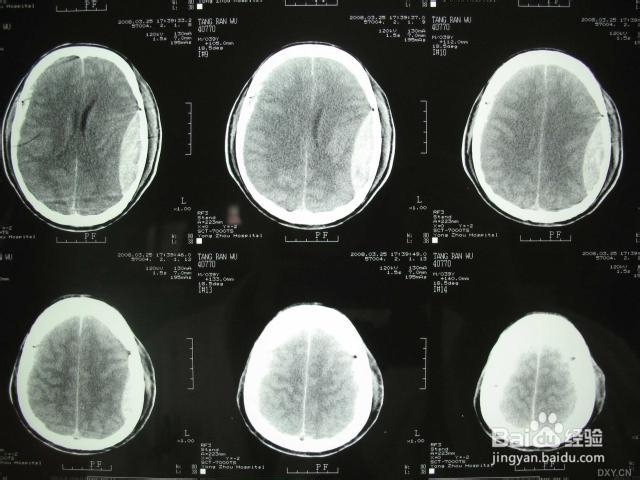

3、 在等待结果的那段时间里,我疯狂地查询资料,想知道最坏的结果是什么。经过查询我发现,头部有肿块在新生儿中很常见。 一般会出现在新生儿头顶稍微靠左或靠右的地方,用手摸时有柔软感,即使摁一下婴儿也不哭,好像并不疼痛 而引起这种情况的原因有两种即产瘤和头颅血肿。产瘤又称为先锋头,是由于孩子在娩出过程中,头部受阴道挤压而发生头皮下局部水肿所致。多在刚出生时最明显,以后逐渐变小,36小时内可完全消失。而头颅血肿则为颅骨骨膜下血管破裂,出血被骨膜局限在局部所致。我的理解是类似于我们大人摔倒后造成的皮下出血。 我家女宝就在拍完片子以后,大夫确诊是在120送医过程中,由于那时候孩子已经到了宫口,于是女儿的头骨和我的骨盆碰撞造成了头部肿块——也就是头部血肿。不需要做什么特殊处理,就好像我们成人摔倒后造成的包块,等着身体慢慢吸收就好了